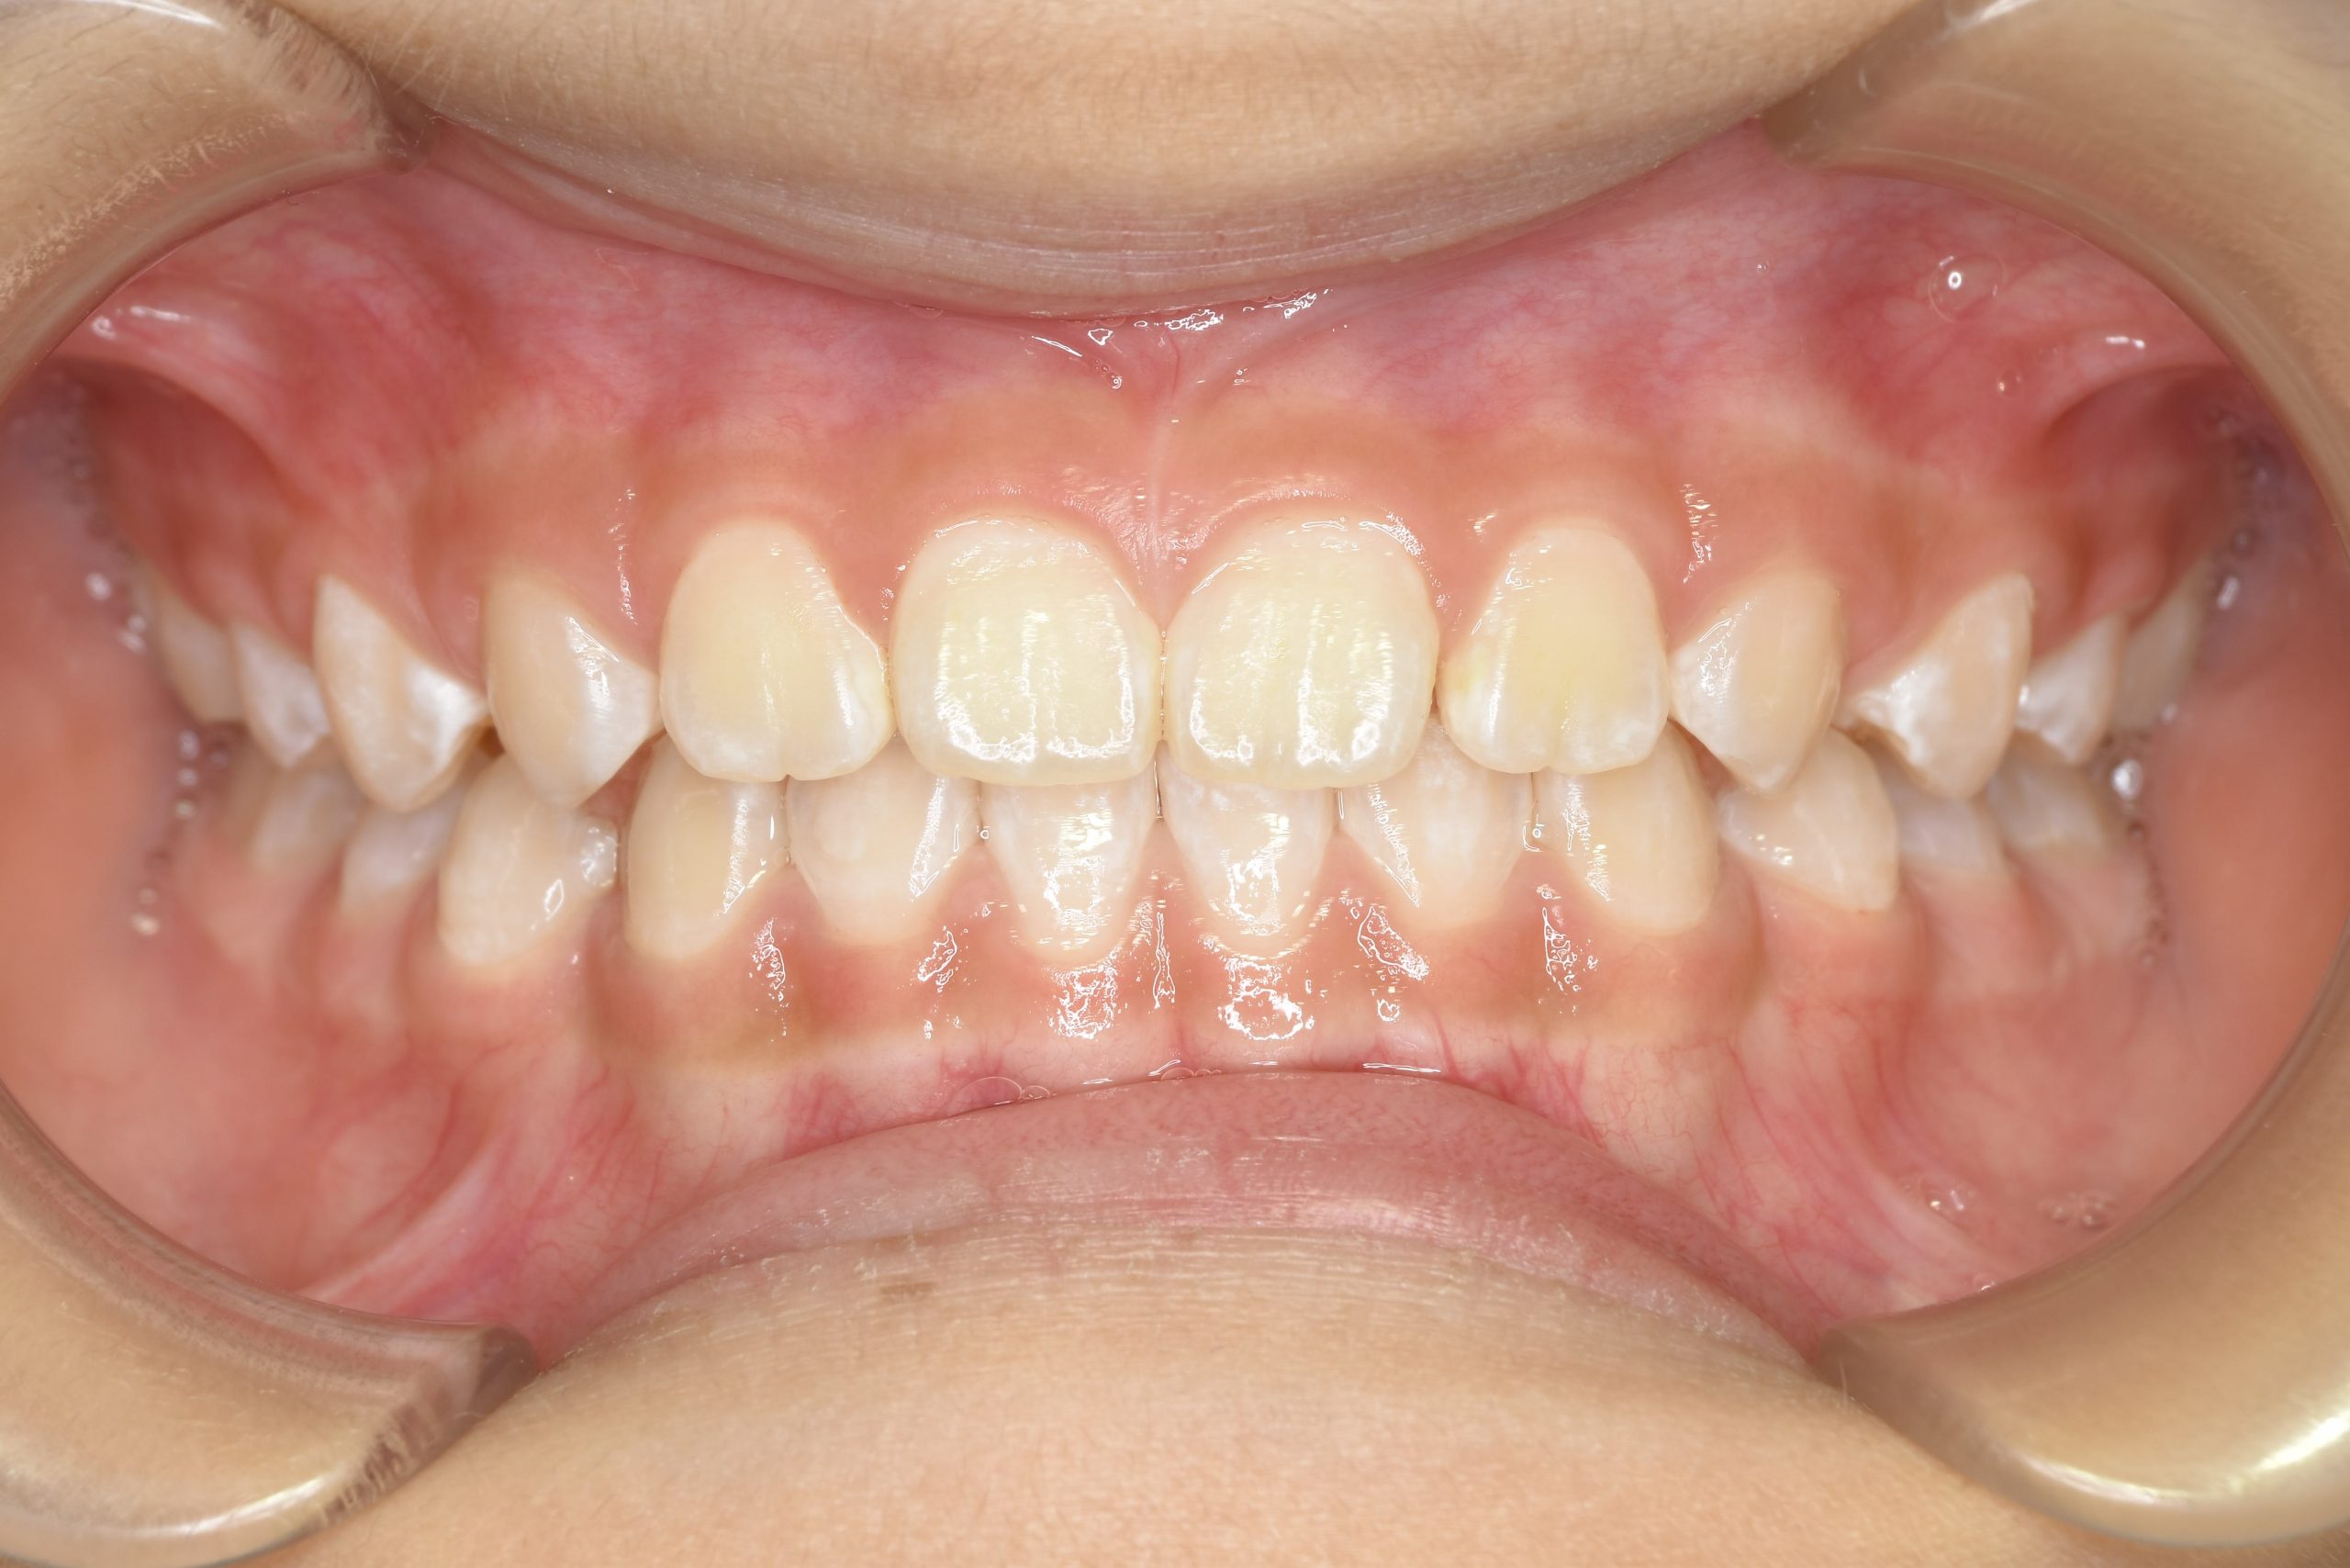

主訴 下顎が出ている

施術内容 上顎急速拡大装置と下顎リンガルアーチを用いて上下顎骨を拡大した。

上顎前方牽引装置を用いて上顎骨を前方に成長促進させた。

その後マウスピース型矯正装置で歯牙を配列し良好な咬合を獲得した。

治癒期間 1年6か月 ※経過観察含む